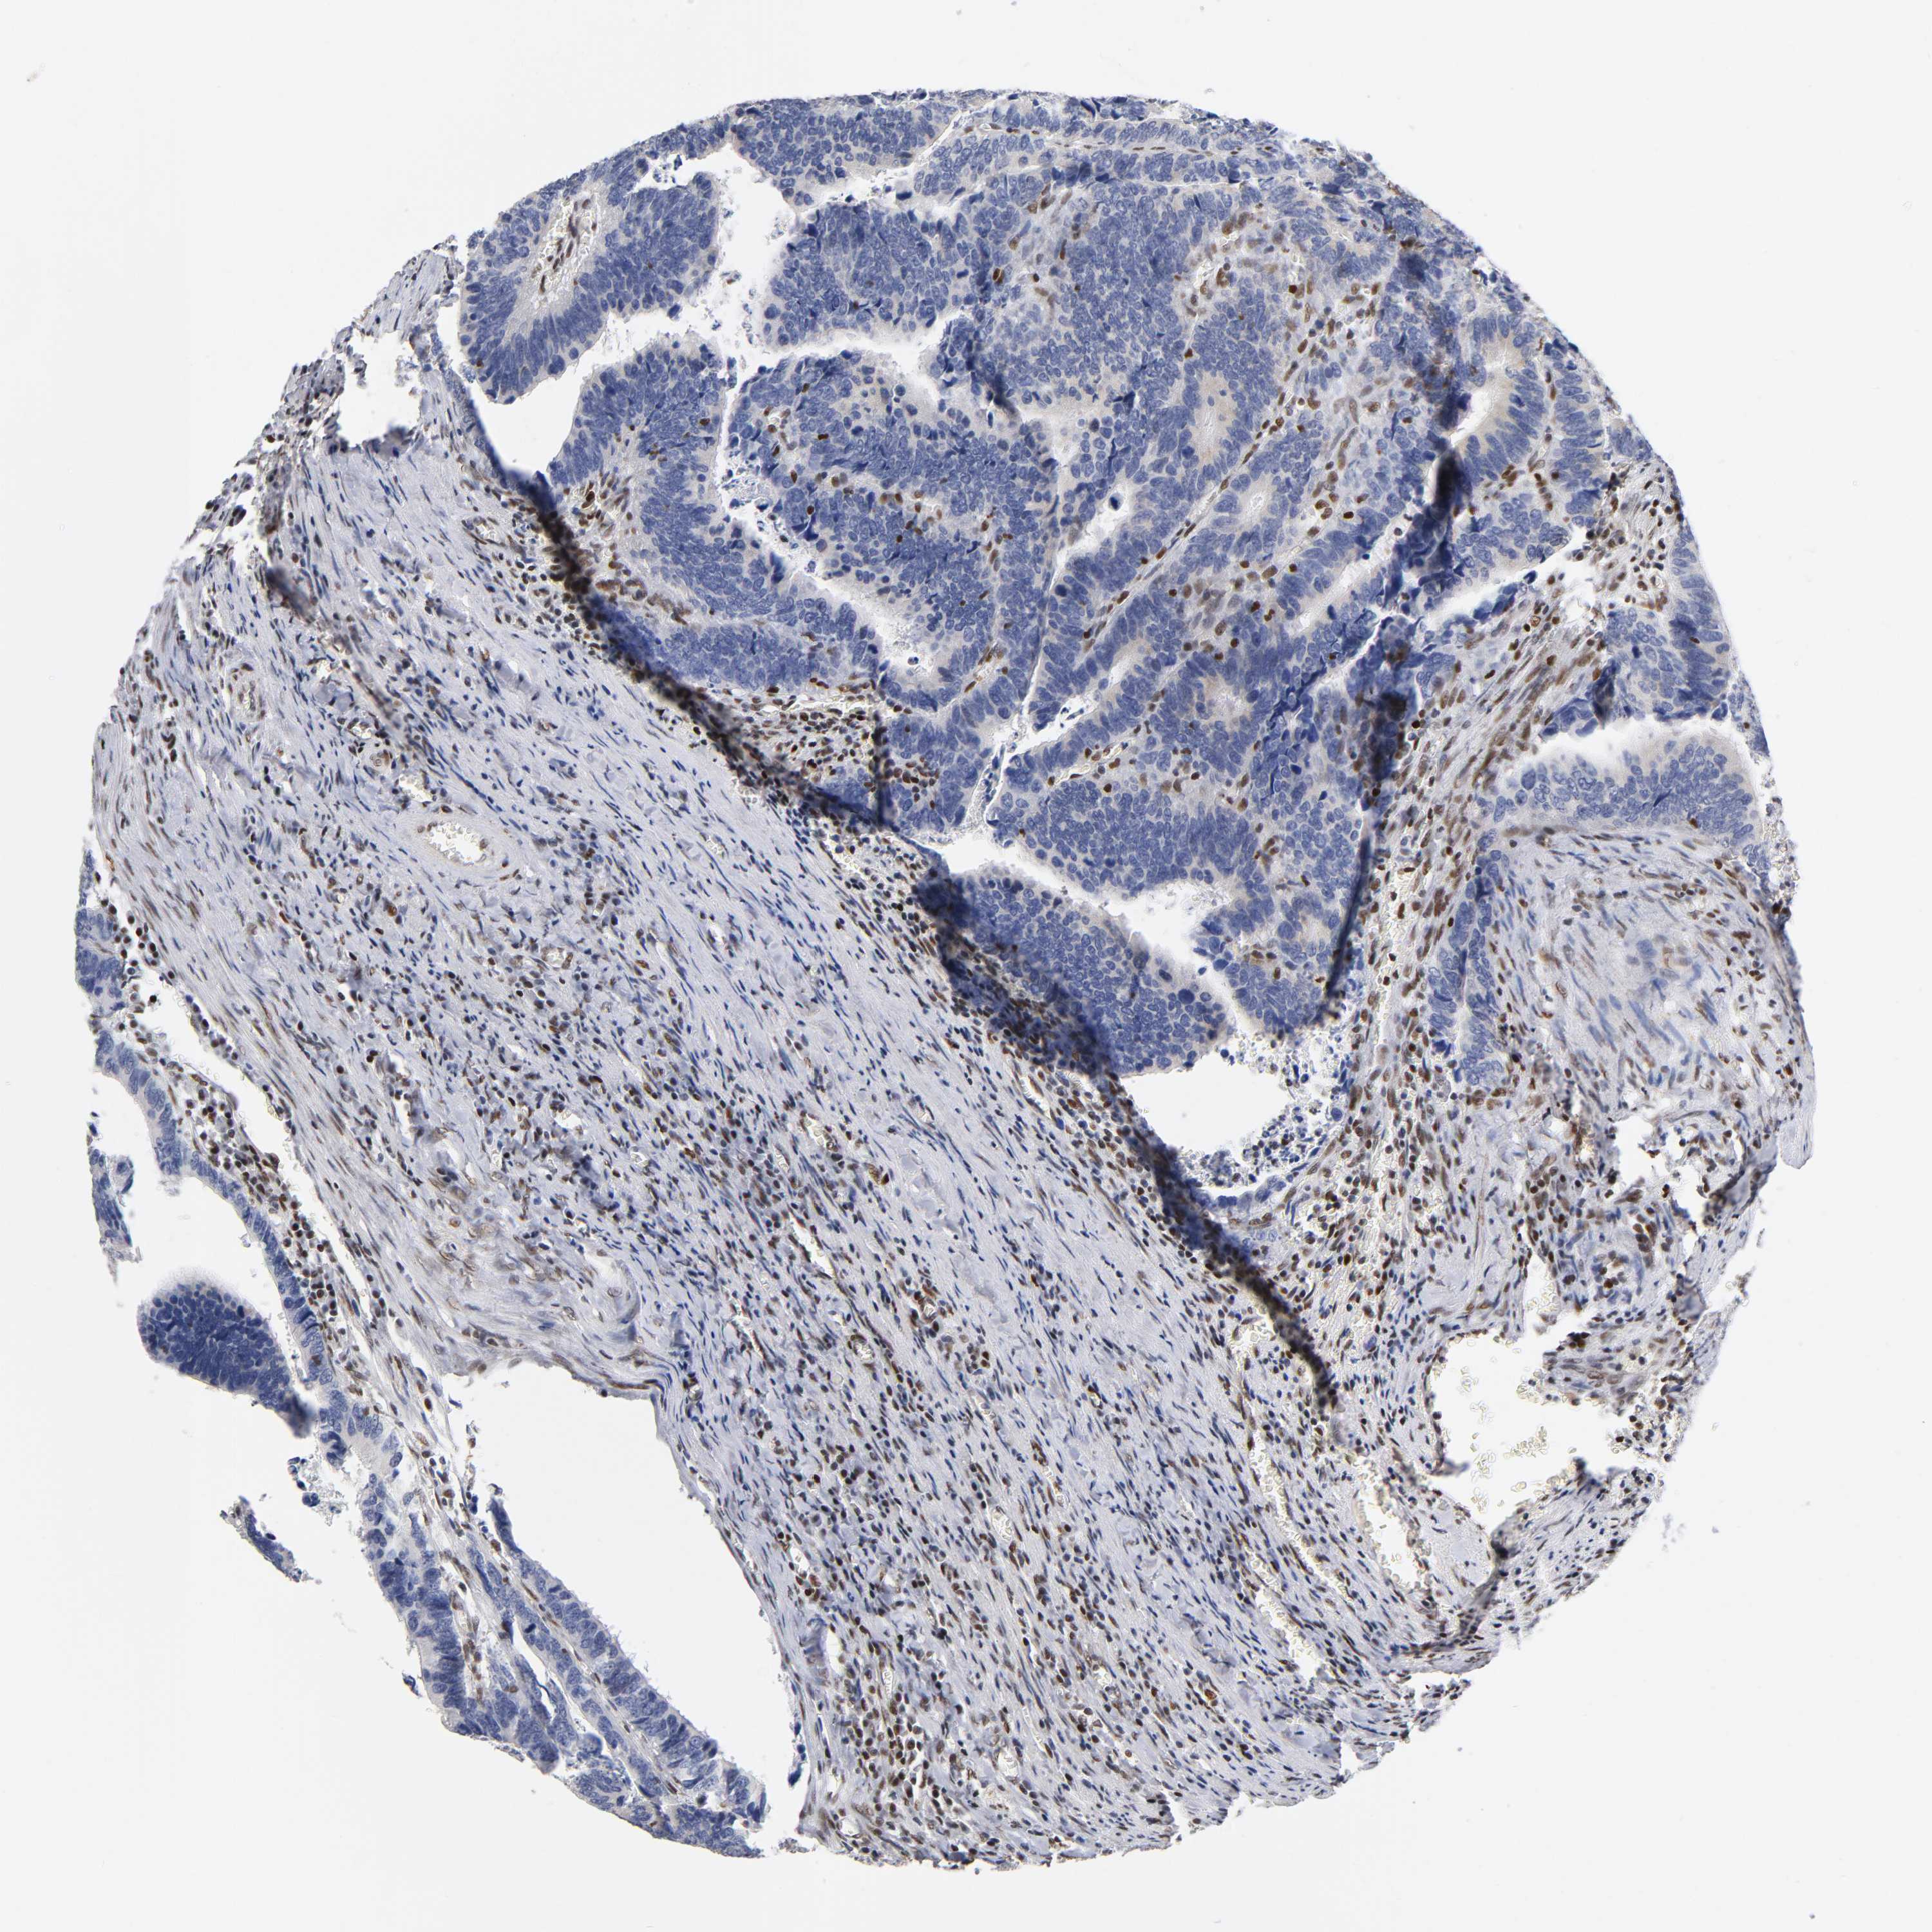

CANCER COLORECTAL CANCER Show tissue menu

Colorectal cancer

Human cancer

Colon adenocarcinoma